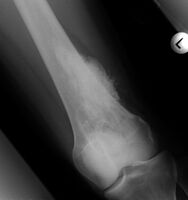

Medical imaging usually shows a well-defined wide-based bony growth on the surface of bone.[5] It can be pedunculated and irregular, giving it a "bizarre" appearance, and is not connected to underlying bone.[2]